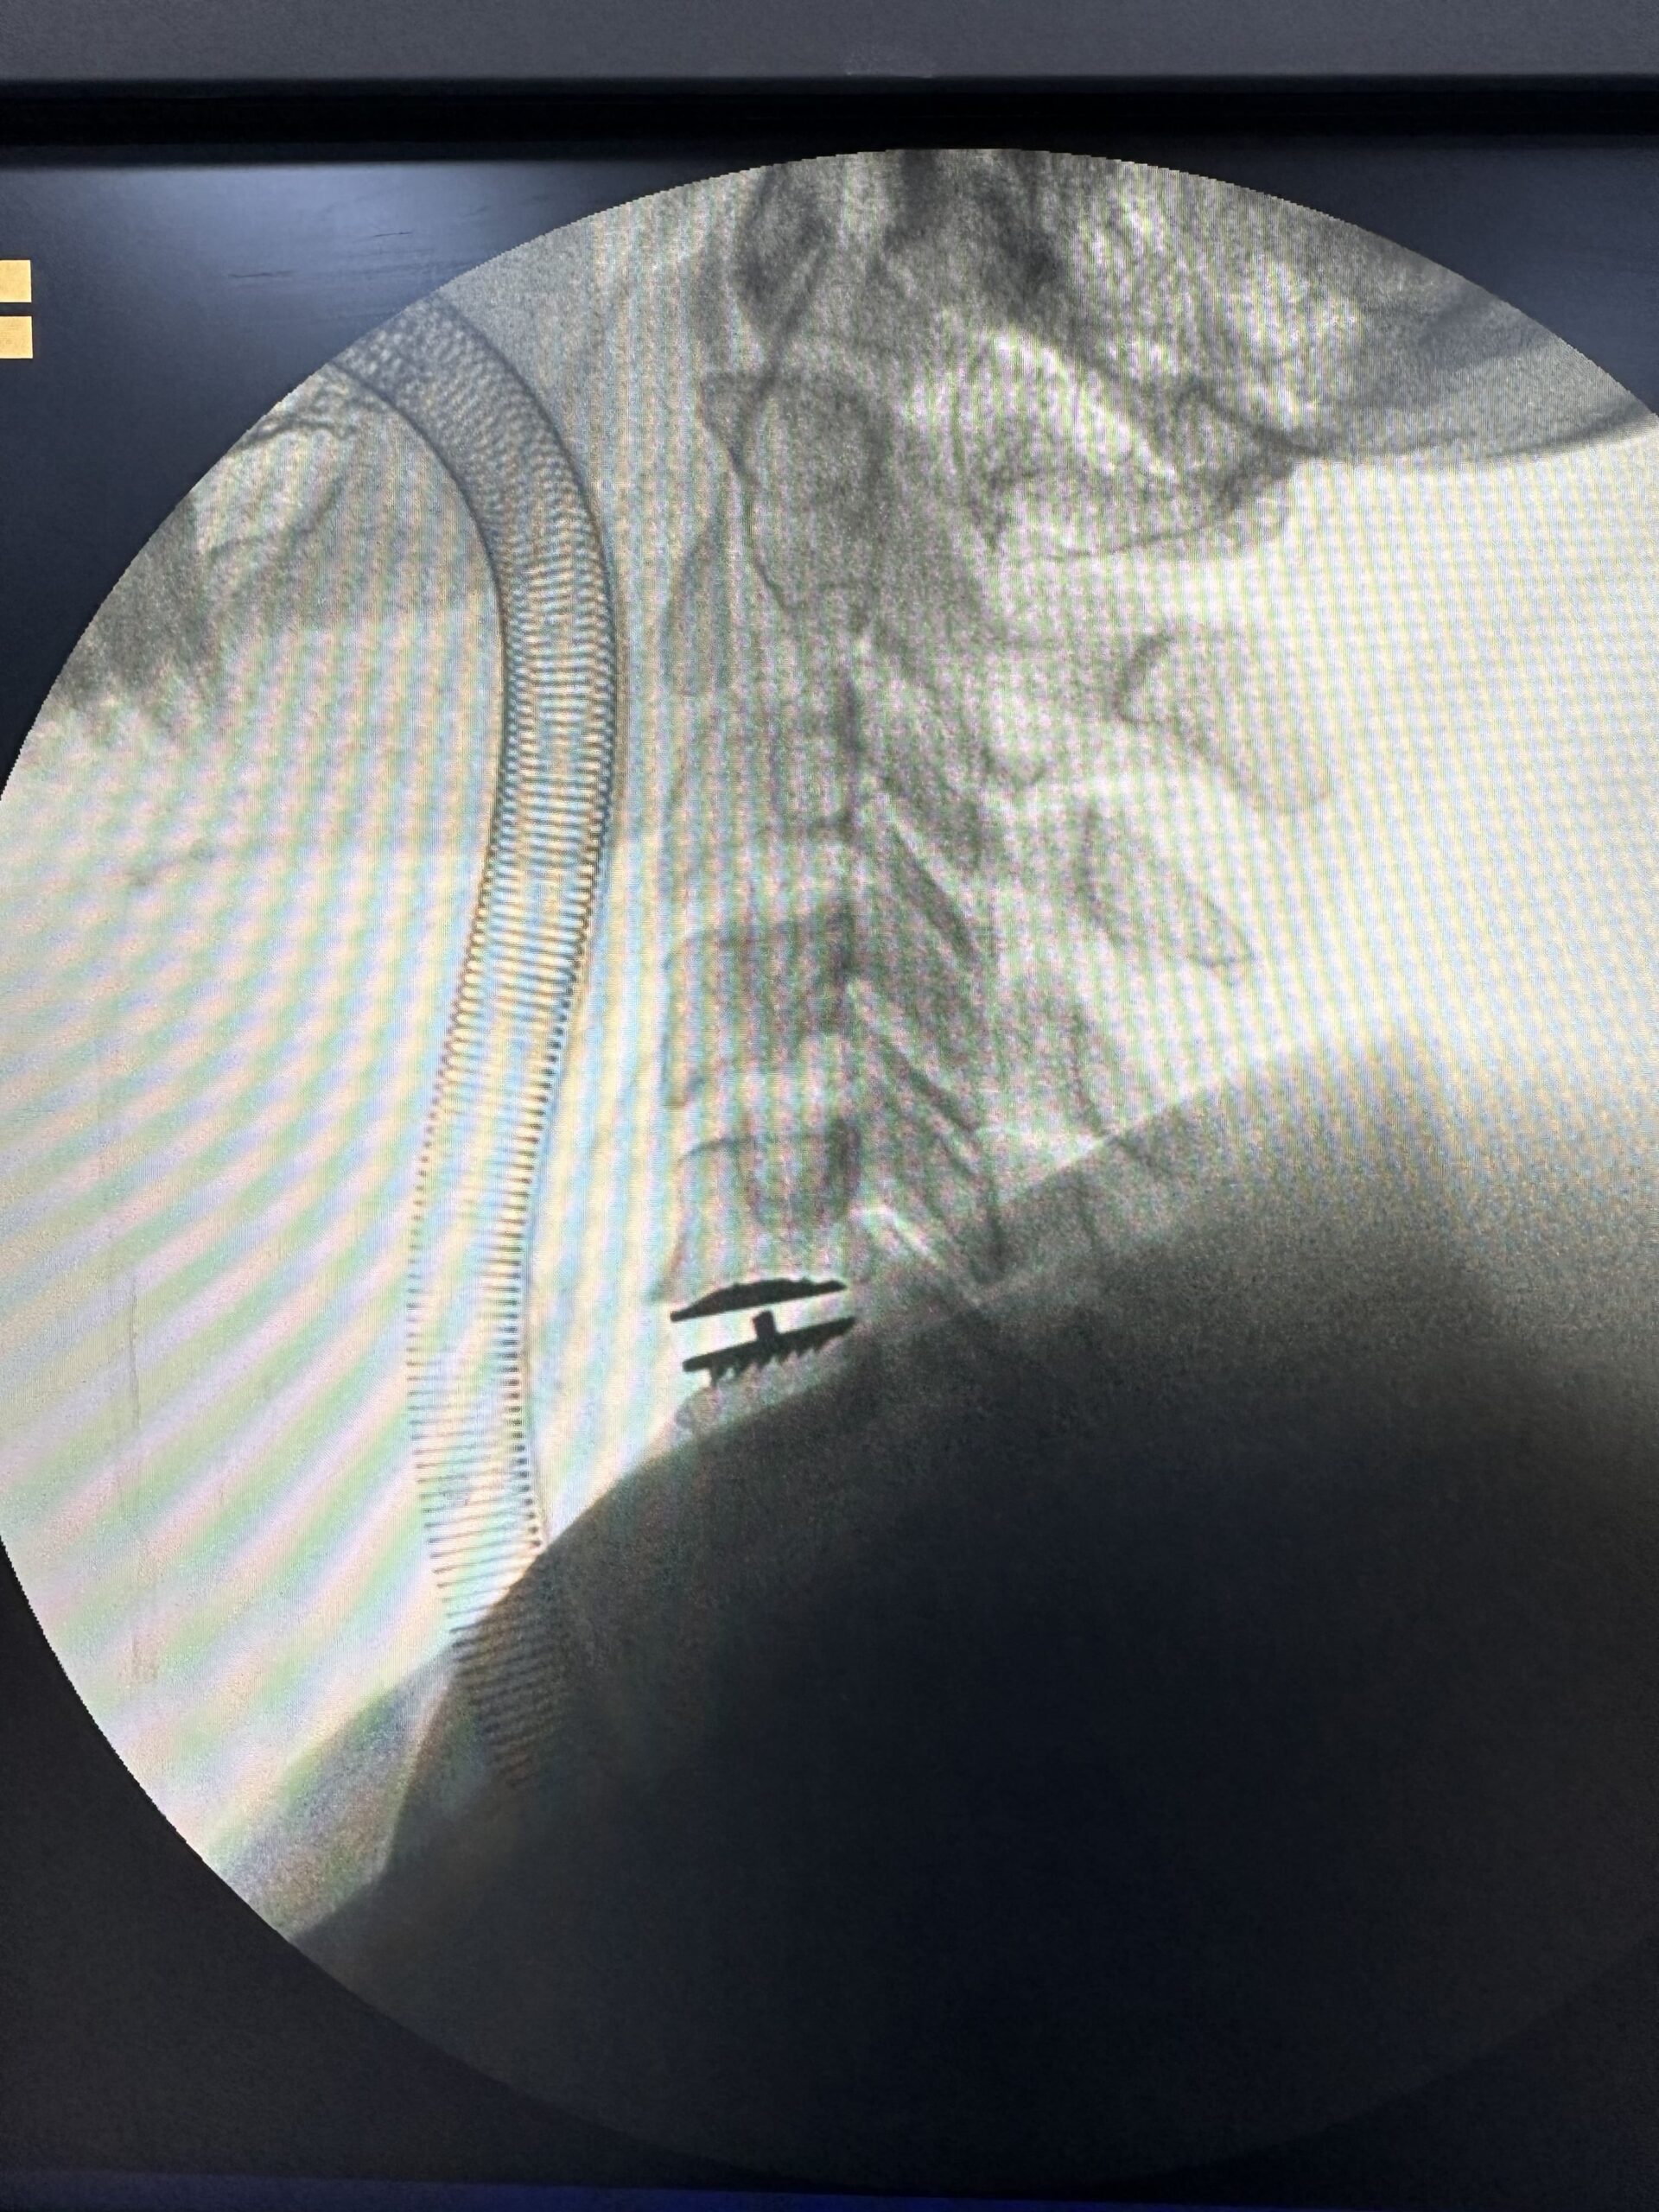

A artrodese cervical é um procedimento cirúrgico que envolve a fusão de duas ou mais vértebras da coluna cervical. A fusão é realizada usando parafusos, pinos ou placas.

A artrodese cervical é indicada para casos de hérnia de disco cervical que não responderam ao tratamento conservador ou que causam dor significativa.

Existem várias técnicas cirúrgicas, o procedimento específico depende da condição do paciente. O Dr. remove discos ou ossos danificados e pode fundir as vértebras afetadas para estabilizar a coluna.